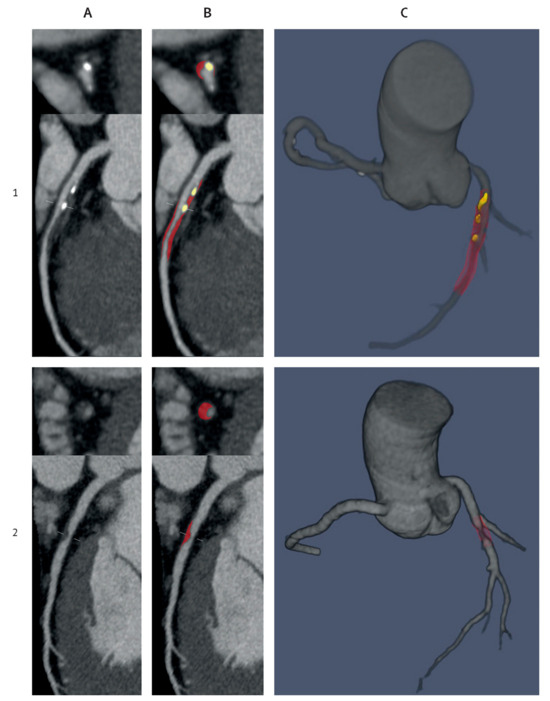

- Lareyre, F.; Adam, C.; Carrier, M.; Dommerc, C.; Mialhe, C.; Raffort, J. A fully automated pipeline for mining abdominal aortic aneurysm using image segmentation. Sci. Rep. 2019, 9, 13750. [Google Scholar] [CrossRef] [PubMed]

- Spinella, G.; Fantazzini, A.; Finotello, A.; Vincenzi, E.; Boschetti, G.A.; Brutti, F.; Magliocco, M.; Pane, B.; Basso, C.; Conti, M. Artificial Intelligence Application to Screen Abdominal Aortic Aneurysm Using Computed tomography Angiography. J. Digit. Imaging 2023, 36, 2125–2137. [Google Scholar] [CrossRef] [PubMed]